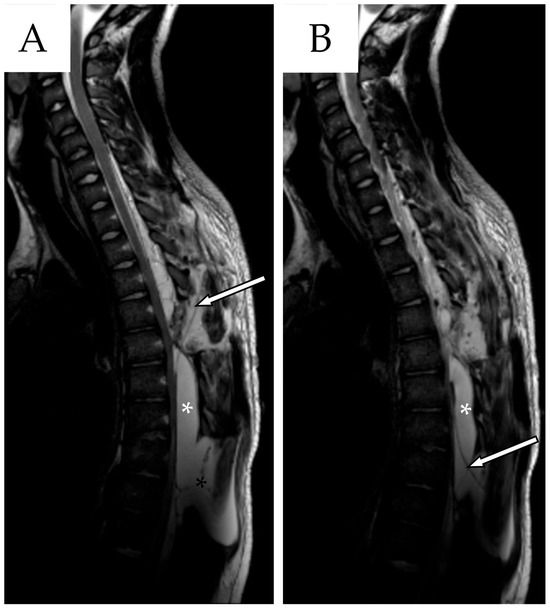

A postoperative MRI demonstrated a mild reduction in cyst volume and clear spinal cord decompression (Figure 3). The patient was enrolled in outpatient rehabilitation and was discharged on postoperative day 10. Upon discharge, the patient demonstrated independent ambulation with minimal aid. Right knee paresthesia had completely resolved. A motor deficit of the right foot persisted, predominantly affecting dorsiflexion (MRC 3/5), with mild residual weakness in plantarflexion.

Figure 3. (A) Postoperative MRI, sagittal section, TSE T2-WI. After T8 laminectomy with cyst fenestration, the spinal cord appeared less compressed at the T7–T8 level (white arrows with black outlines). Fenestration was confirmed by the presence of an air sac within the caudal portion of the SAC (black asterisk). The yellow line indicates the level at which the axial section in (B) was obtained. (B) The spinal cord, although not yet re-expanded, appeared less compressed.

At the routine outpatient follow-up visit two weeks after discharge, urinary function had fully recovered. However, the control thoracic spine MRI revealed enlargement of the residual cystic components, both cranially at T2–T4 and caudally at T8–T9, adjacent to the previous fenestration site. Additionally, an 8.5 cm pseudomeningocele was identified, along with spinal cord signal changes between T5 and T8 (Figure 4). Given the clinical stability despite the MRI findings, a decision was made to continue close follow-up, with repeat imaging scheduled in two weeks.

Figure 4. First follow-up MRI, sagittal section, TSE T2-WI. Both the cranial (red asterisk) and caudal (white asterisk) components of the SAC appear enlarged compared to the MRI in Figure 3, especially the latter. Additionally, a new pseudomeningocele (black asterisk) is visible at the level of the previous fenestration.